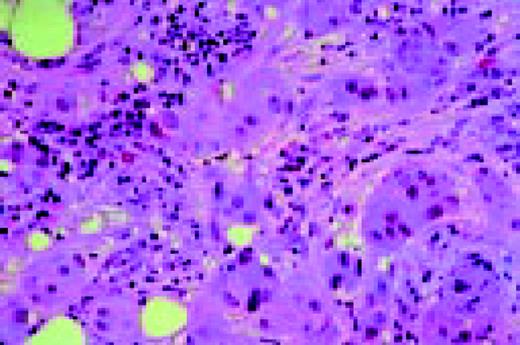

Slide E9

Agnogenic myeloid metaplasia with myelofibrosis, low-magnification, BMB, reticulin stain. This H&E-stained preparation shows virtual replacement of the marrow cavity with light pink-staining fibrosis tissue. A reticulin stain (2) demonstrates the fibrosis as well.FIG105